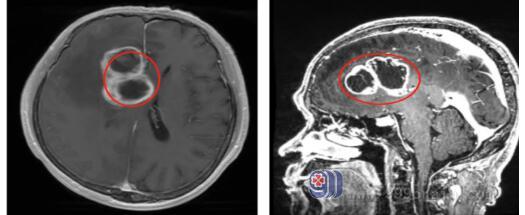

广东三九脑科医院神经外十科医生接诊后,为叶女士安排了头颅MRI检查,MRI结果显示:“右侧额顶叶巨大占位性病变及脑疝形成”。这时叶女士的病情已非常严重,神经外十科主任欧阳辉教授认为,患者颅内病变属于肿瘤性病变,怀疑是高级别胶质瘤;术前脑电图也考虑患者的癫痫是高级别胶质瘤所致,他指示医疗团队尽快进行手术切除肿瘤,降低颅内压,手术抢救叶女士。

完善术前准备后,神经外十科团队为叶女士紧急进行了“右侧额顶叶巨大高级别胶质瘤切除术+硬脑膜修补术+颅骨成形术”,术中采用导航定位右额-颞岛叶肿瘤组织,在高清显微镜下将肿瘤全切除。术中病理为冰冻结果为高级别胶质瘤。